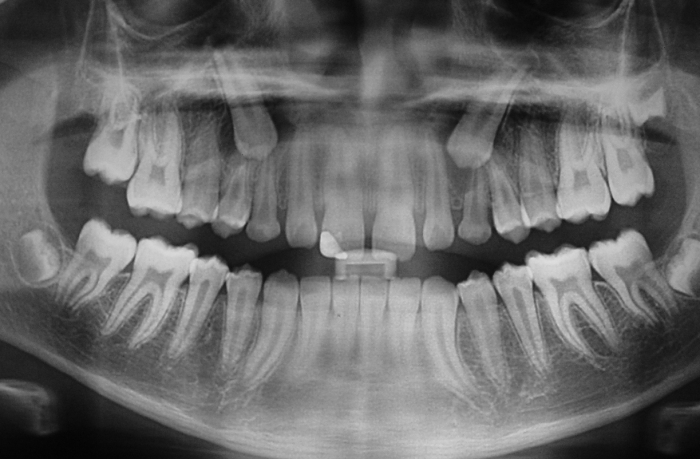

Rx Panorâmico - Caninos respondendo ao tracionamento - Clínica Cliniface

Rx Panorâmico - Caninos respondendo ao tracionamento